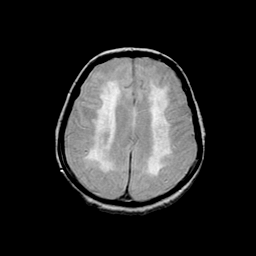

Basal Ganglia Calcification: proton density-weighted MR -- Slice #12

[Home][Help][Clinical] Slice 12